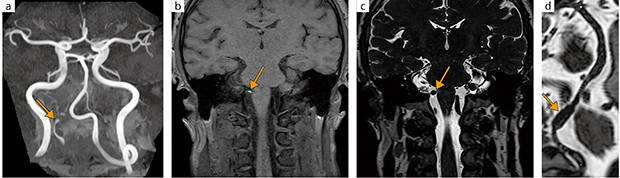

「TOF-MRAとisoFSEの画質が非常に優れており,DWIも良好です。特にisoFSEは,脳脊髄液のアーチファクトが出にくく,血管壁そのものを観察しやすいため,ほかの装置では評価が困難であった椎骨動脈解離の出血がTRILLIUM OVALでとらえられた症例も経験しています。脳梗塞,脳出血,脳動脈解離など血管評価において,TRILLIUM OVALはなくてはならないものとなっています。また,BeamSatについては,レジストレーションの向上など課題はありますが,選択的に血管を描出することができるため,もやもや病や動脈硬化に対するバイパス術後の評価に有用です。Balanced SARGEシーケンスはアーチファクトも少なく,聴神経腫瘍や神経血管圧迫症候群といった病態の評価において,今後活用できると期待しています」

症例 40歳代,男性,右椎骨動脈解離

MRA(a)にて右椎骨動脈V4に狭窄および限局性の拡張(→)が描出されている。T1 isoFSE(b)では右椎骨動脈にintramural hematomaを示唆する高信号域(←)が認められ,T2 isoFSE(c)では紡錘状拡張が描出されている(←)。この拡張は,CPR像(d)にてより明瞭に 確認できる(→)。TRILLIUM OVALは,TOF-MRAとisoFSEの画質に優れている。血管壁を評価しやすいため脳動脈解離の診断に有効である。